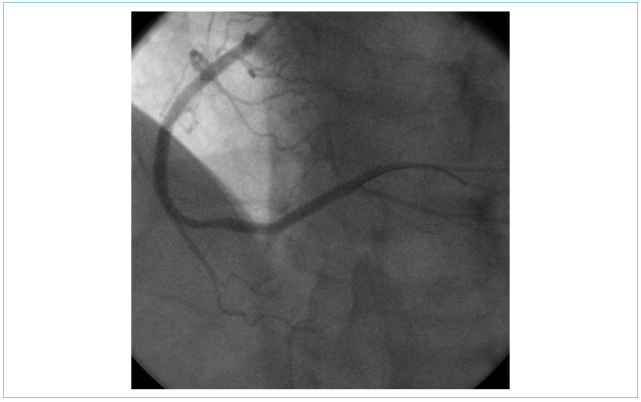

После реканализации ПКА имплантированы стенты с антипролиферативным покрытием с хорошим непосредственным ангиографическим результатом (рис. 7).

Рисунок 7. Контрольная ангиография после стентирования правой коронарной артерии

Figure 7. Control angiography after the right coronary artery stenting